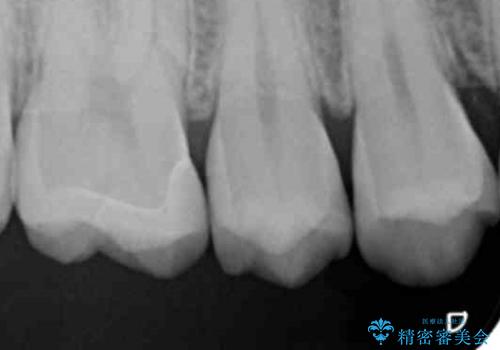

歯と歯の間の虫歯 セラミックインレーでの治療

歯と歯の間に虫歯があったためセラミックインレーで治療をしていきました。

- 右上6 セラミックインレー 77,000円費用は治療当時の料金となります

歯と歯の間は虫歯の好発部位となっています。

今後の虫歯リスクを抑えるためにも適合の良い補綴物を装着することは有効です。